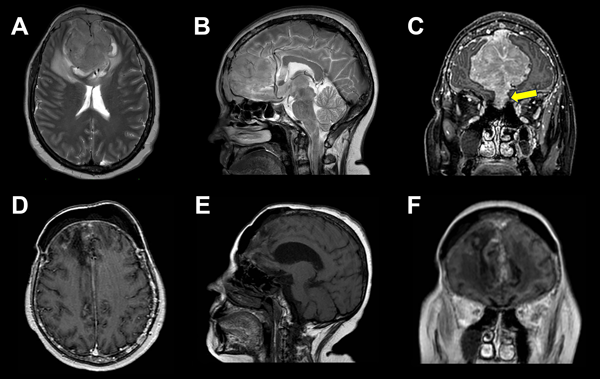

Figura 2. A, B, C) RM preoperatoria. A) Corte axial en secuencia T2, lesión isointensa con marcado edema perilesional. B) Corte sagital en secuencia T2, arterias pericallosas desplazadas. C) Corte coronal en secuencia T1, lesión extraaxial con realce homogéneo a la administración de contraste. Invasión de los senos etmoidales (flecha amarilla). D, E, F) RM postoperatoria, en corte axial sagital y coronal se evidencia lodge de resección de LOE bifrontal sin remanente lesional y huella de craneoplastia.

A los 2 meses de la intervención quirúrgica, se realizó RM de encéfalo, donde se observó huella de craniectomía bifrontal con presencia de material de craneoplastia, subyacente a la misma colección extraaxial de aproximadamente 9 mm de espesor. Presentó área secuelar corticosubcortical en el parénquima frontal adyacente a la línea media con restos hemáticos en degradación que se extendía en profundidad hasta el margen ventricular con compromiso de la sustancia gris y blanca. Sin evidencia de remanente lesional.